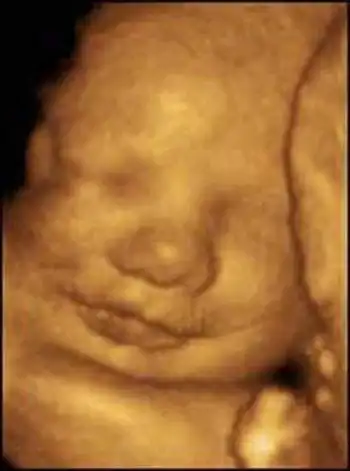

Создатель этой системы профессор Стюарт Кэмпбелл, один из ведущих акушеров Соединенного Королевства, стал знаменитостью в мире медицины благодаря снимкам, на которых зародыш улыбается (раньше считалось, что эта способность появляется лишь после рождения)...

Качество изображений превосходное!...

Специалисты признают, что эти снимки, прежде всего помогающие оценить правильность развития плода, завораживают...

На 10-й неделе лицо полностью сформировалось, но глаза еще закрыты. Кишечник удлиняется и закручивается в петли. Плод уже может глотать. Оба полушария головного мозга уже есть, начинает развиваться мозжечок.

На 11-й неделе продолжается окостенение скелета. Развиваются эндокринные железы и лимфоузлы. Сердце бьется с частотой 130-150 ударов в минуту. 9-сантиметровый ребенок двигает головой, руками, ногами, сжимает кулачки, поворачивает голову и даже пробует сосать свой палец.

12-я неделя. Оформились веки, мочки ушей, на пальчиках уже растут ноготки. Ребенок морщит губы, открывает и закрывает рот, может всасывать и глотать жидкость, которая его окружает.